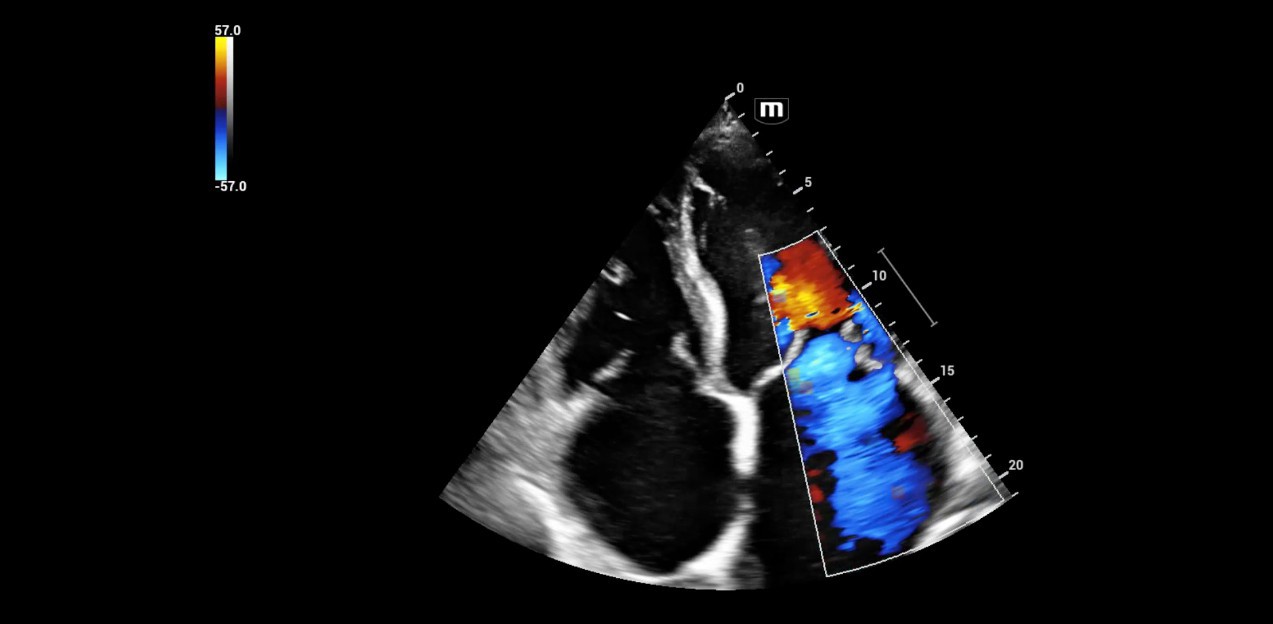

When working in an intensive care unit, obtaining a quick overview of a patient's health status is crucial. Sonography can non-invasively image multiple entities, some of which may be critical, in real-time. However, using this technology requires equipment that offers high flexibility without compromising image quality. For his department, specialized intensive care physician Dr. Armin Seibel relies on the high-end color Doppler ultrasound device Resona I9 from Mindray, which offers exceptional image quality, multifunctionality, and a long battery life.

Diverse application possibilities

Dr. Seibel chose Resona I9 for various reasons. First, the high-end device offers excellent image quality with high resolution, as well as focused examination techniques that facilitate diagnosis. For instance, he frequently uses contrast-enhanced ultrasound (CEUS) to clarify uncertain findings.